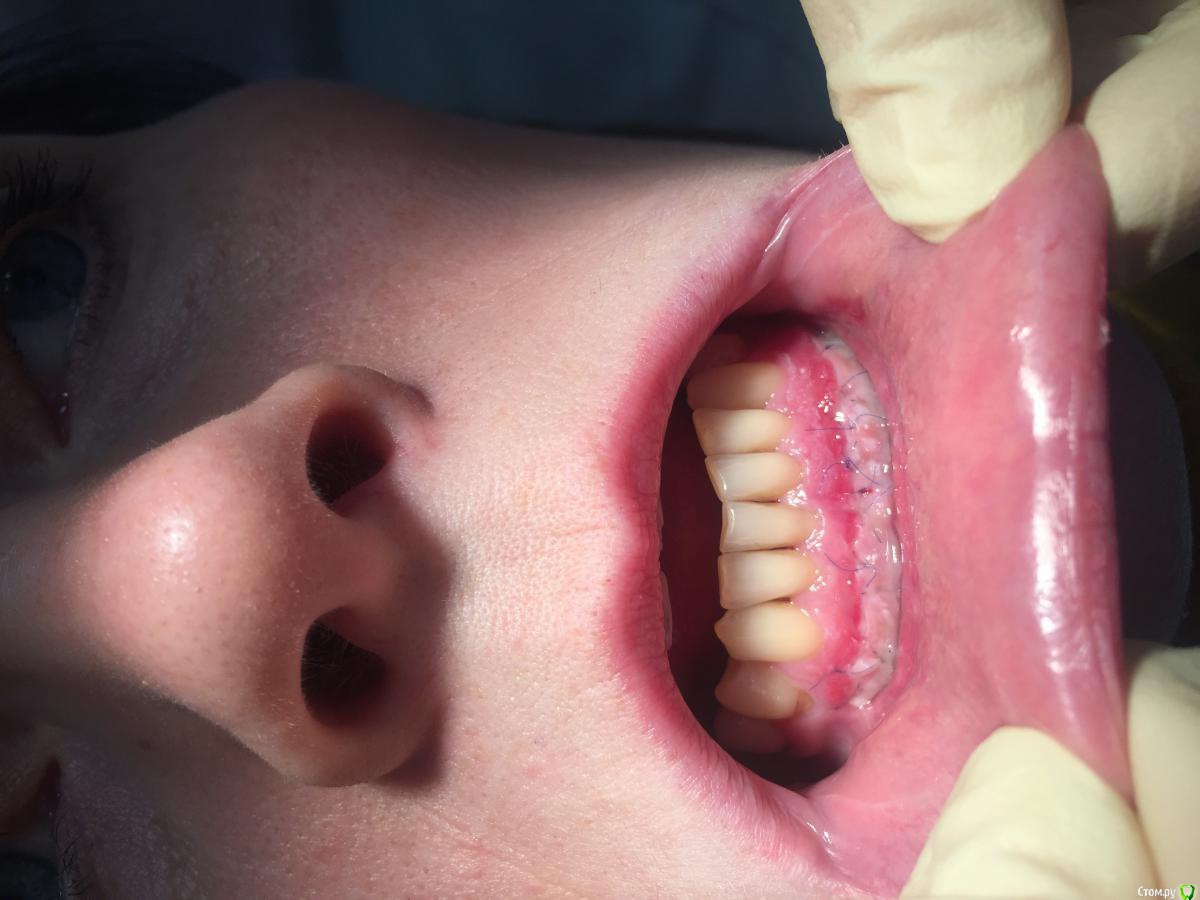

Dr.Safiullin Опубликовано 12 мая, 2017 Поделиться Опубликовано 12 мая, 2017 (изменено) Добрый вечер всем, решил тоже свой первый, небольшой кейс выложитьСильно не ругайте, полгода как получил диплом) Вопрос: 1)Нужно ли подшивать губу? Я не подшил, потому что в гос. времени мало на приём, да и испугался надкостницу травмировать лишний раз. А то боялся получить рубец, хотя не получил его!) 2) на 5 фотке это десквамация? Приветствуются конструктивная критика! Спасибо Изменено 12 мая, 2017 пользователем Dr.Safiullin Ссылка на комментарий

Dr.Safiullin Опубликовано 13 мая, 2017 Автор Поделиться Опубликовано 13 мая, 2017 Доктор, вы прекрасно провели ненужную и бесполезную операцию )) Тут не было показаний для вестибулопластики.Может быть, но а как же преддверие 1.5-2мм, тонкий биотип десны, рецессия по 3 классу по Миллеру в области фронтальных зубов? Из за скученность тоже убыль, но все же. Вот тут может быть информативнее будет Ссылка на комментарий

колесников Опубликовано 13 мая, 2017 Поделиться Опубликовано 13 мая, 2017 (изменено) Прелестное было преддверие. Обратить внимание следовало на особенности прикуса, выявить в анамнезе бруксизм, местно -суперконтакты. Думаю причина рецессии в перегрузке.Кстати подшивать лоскут надо было к кератинизированой слизистой,тогда не было бы диссонанса в цвете в виде зебры ,в окончательном варианте Изменено 13 мая, 2017 пользователем колесников Ссылка на комментарий

Bier Опубликовано 13 мая, 2017 Поделиться Опубликовано 13 мая, 2017 у зубов по 2мм кератинизированной десны. Причина не в ее дефиците. Преддверие было нормальным. Ссылка на комментарий